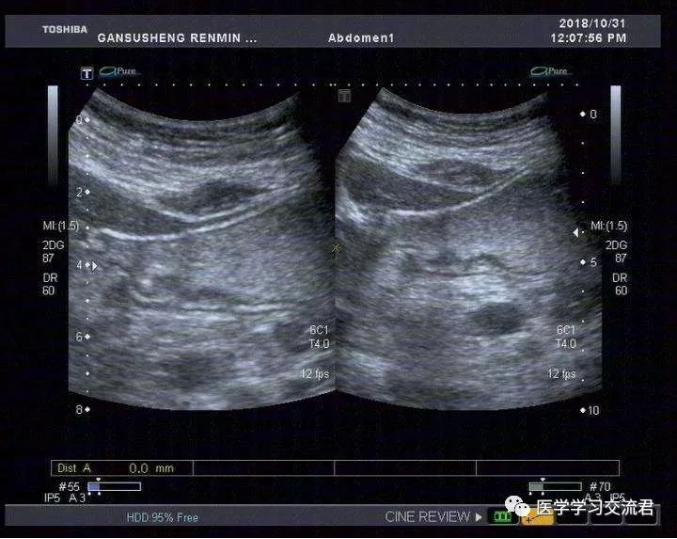

NO.3【胃肠超声造影】

嘱患者饮胃肠造影剂1000ml后扫查:胃贲门及幽门造影剂通过顺畅,胃窦后壁胃壁局限性不均匀增厚,累计长度约19.8mm,最厚处7.4mm,粘膜面连续性中断,可见6mm粘膜凹陷,其内见强回声斑附着,粘膜下层连续完整,局部胃蠕动僵硬,造影剂通过顺畅,余胃壁各层次清楚,粘膜光滑连续,蠕动良好,未见明显肿块及溃疡灶,十二指肠球部充盈好,内未见异常回声。

诊断:胃窦后壁胃壁局限性不均匀增厚并溃疡形成

根据2010年国际抗癌联盟/美国癌症联合委员会ICC/AJCC)TNM 分期标准并结合正常胃壁声像图表现得出超声下T分期标准:T1—病变局限于胃壁前三层(强—弱—强)回声线,未突破第三层强回声线;T2—病变侵及胃壁第四层弱回声线,但尚未突破该层结构;T3—病变侵及第五层强回声线但尚未中断;T4—病变突破第五层强回声线,甚至侵犯胃周组织。早期胃癌超声造影图像主要表现为:病变处胃壁局限性不均匀性增厚,回声减低,稍隆起于胃腔内或呈浅凹陷,局部胃壁黏膜层和黏膜肌层破坏、层次不清,与周围正常黏膜界限不清,黏膜表面不光滑或粗糙不平,有时可出现浅而大的黏膜凹陷,深可达黏膜下层,凹陷周缘胃壁水肿增厚,凹陷底部较宽而平,表面常附有不规则强回声斑,病变处胃壁蠕动减弱,局部有僵硬感。